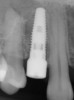

In order to maximize the height of the peri-implant papilla, significant efforts must be made to maximize the blood supply and to preserve the bone on the adjacent roots and between the implant.12 Pressure and blanching of the peri-implant tissues compromises the blood supply of this fragile complex and (eventually) leads to reduction in the height of the papilla (Figure 3). At a given site in a given individual, there is a natural biologic width that the body will strive to maintain between any bone and any non-integrated material. Thus, if a non-integrating abutment is placed within close proximity to the bone on the adjacent natural tooth (Figure 4), inevitably the bone will be remodeled to a more apical position to re-establish the biologic width. This distance obviously varies, but generally 1 mm to 1.5 mm is needed.13

Fig 4. Flared abutments (healing or definitive) that encroach on the biologic width of the peri-implant bone will also result in apical remodeling. This is likely to compromise the critical crest of bone on the adjacent teeth that is largely responsible for supporting the papilla.